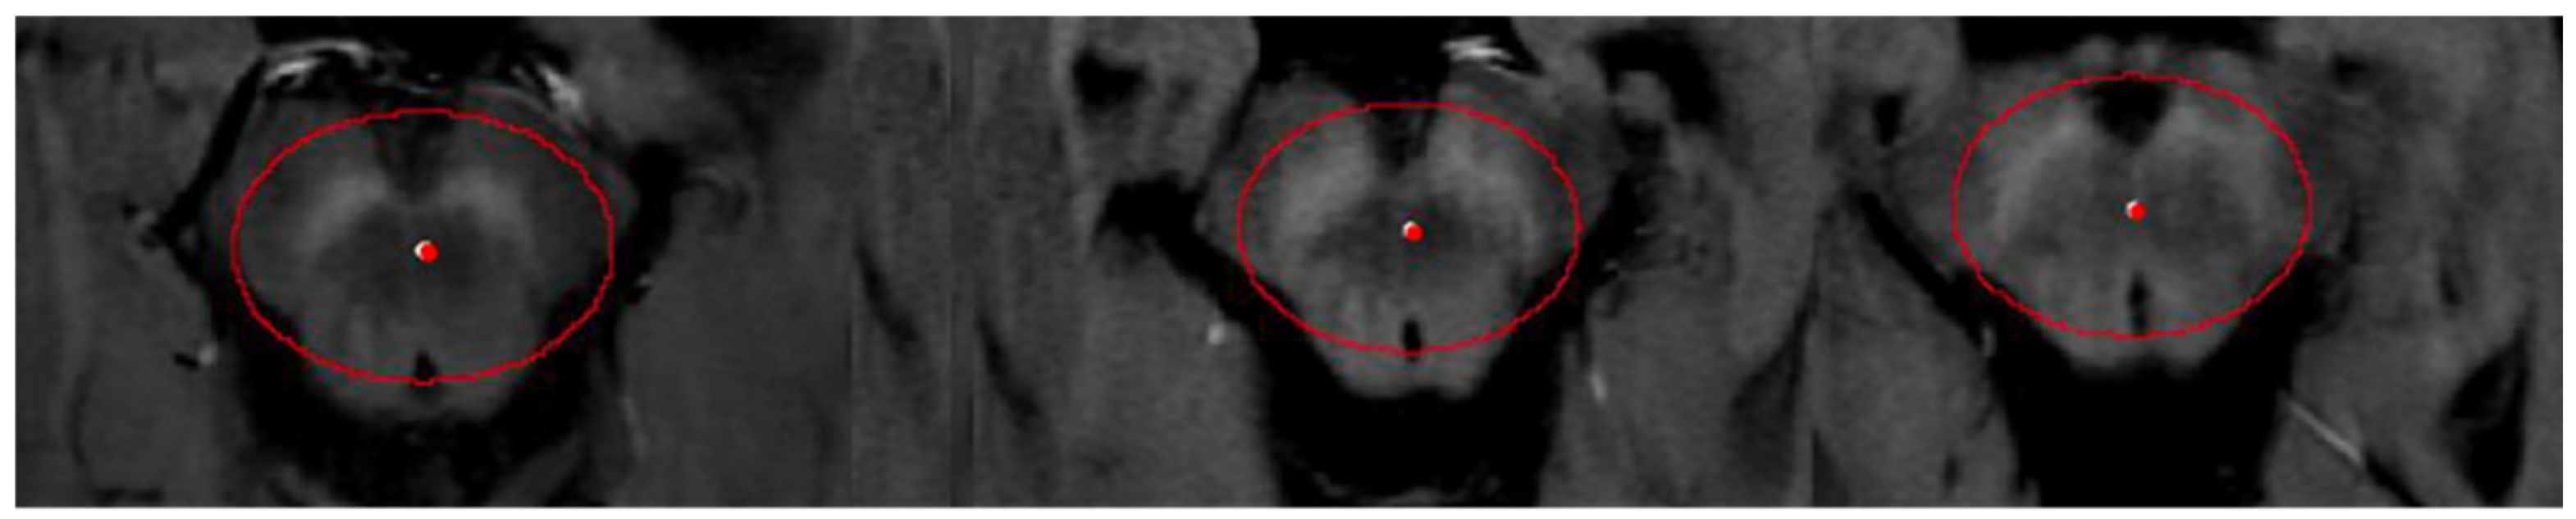

2.4.1. Semi-Automated Segmentation

2.4.2. Mean Midbrain Intensity Quantification

2.4.3. Volume Measurement

2.4.4. Volume Correction